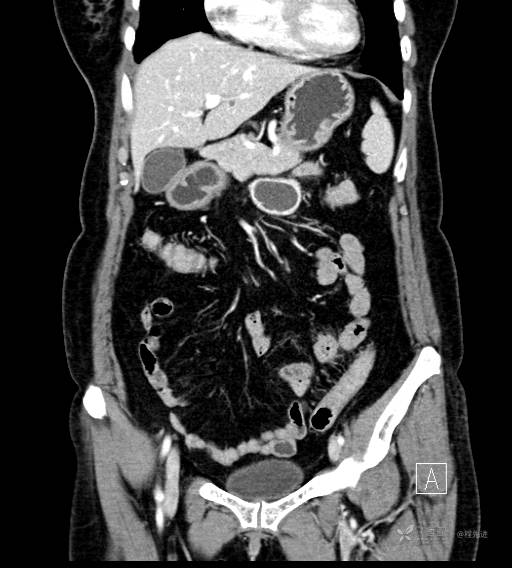

CT平扫